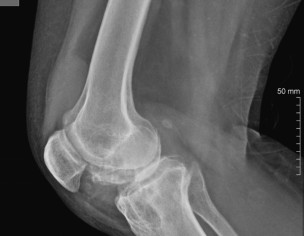

Not sure which treatment you are referring to. the Xrays show quite a bit of damage for someone who is just 40 yrs old. I suspect the patient may have inflammatory arthritis causing this. for this she should consult a qualified Rheumatologist for specialist treatment

I agree with Dr. Ashar, you are too young to have these x rays. See a rheumatologist soon.